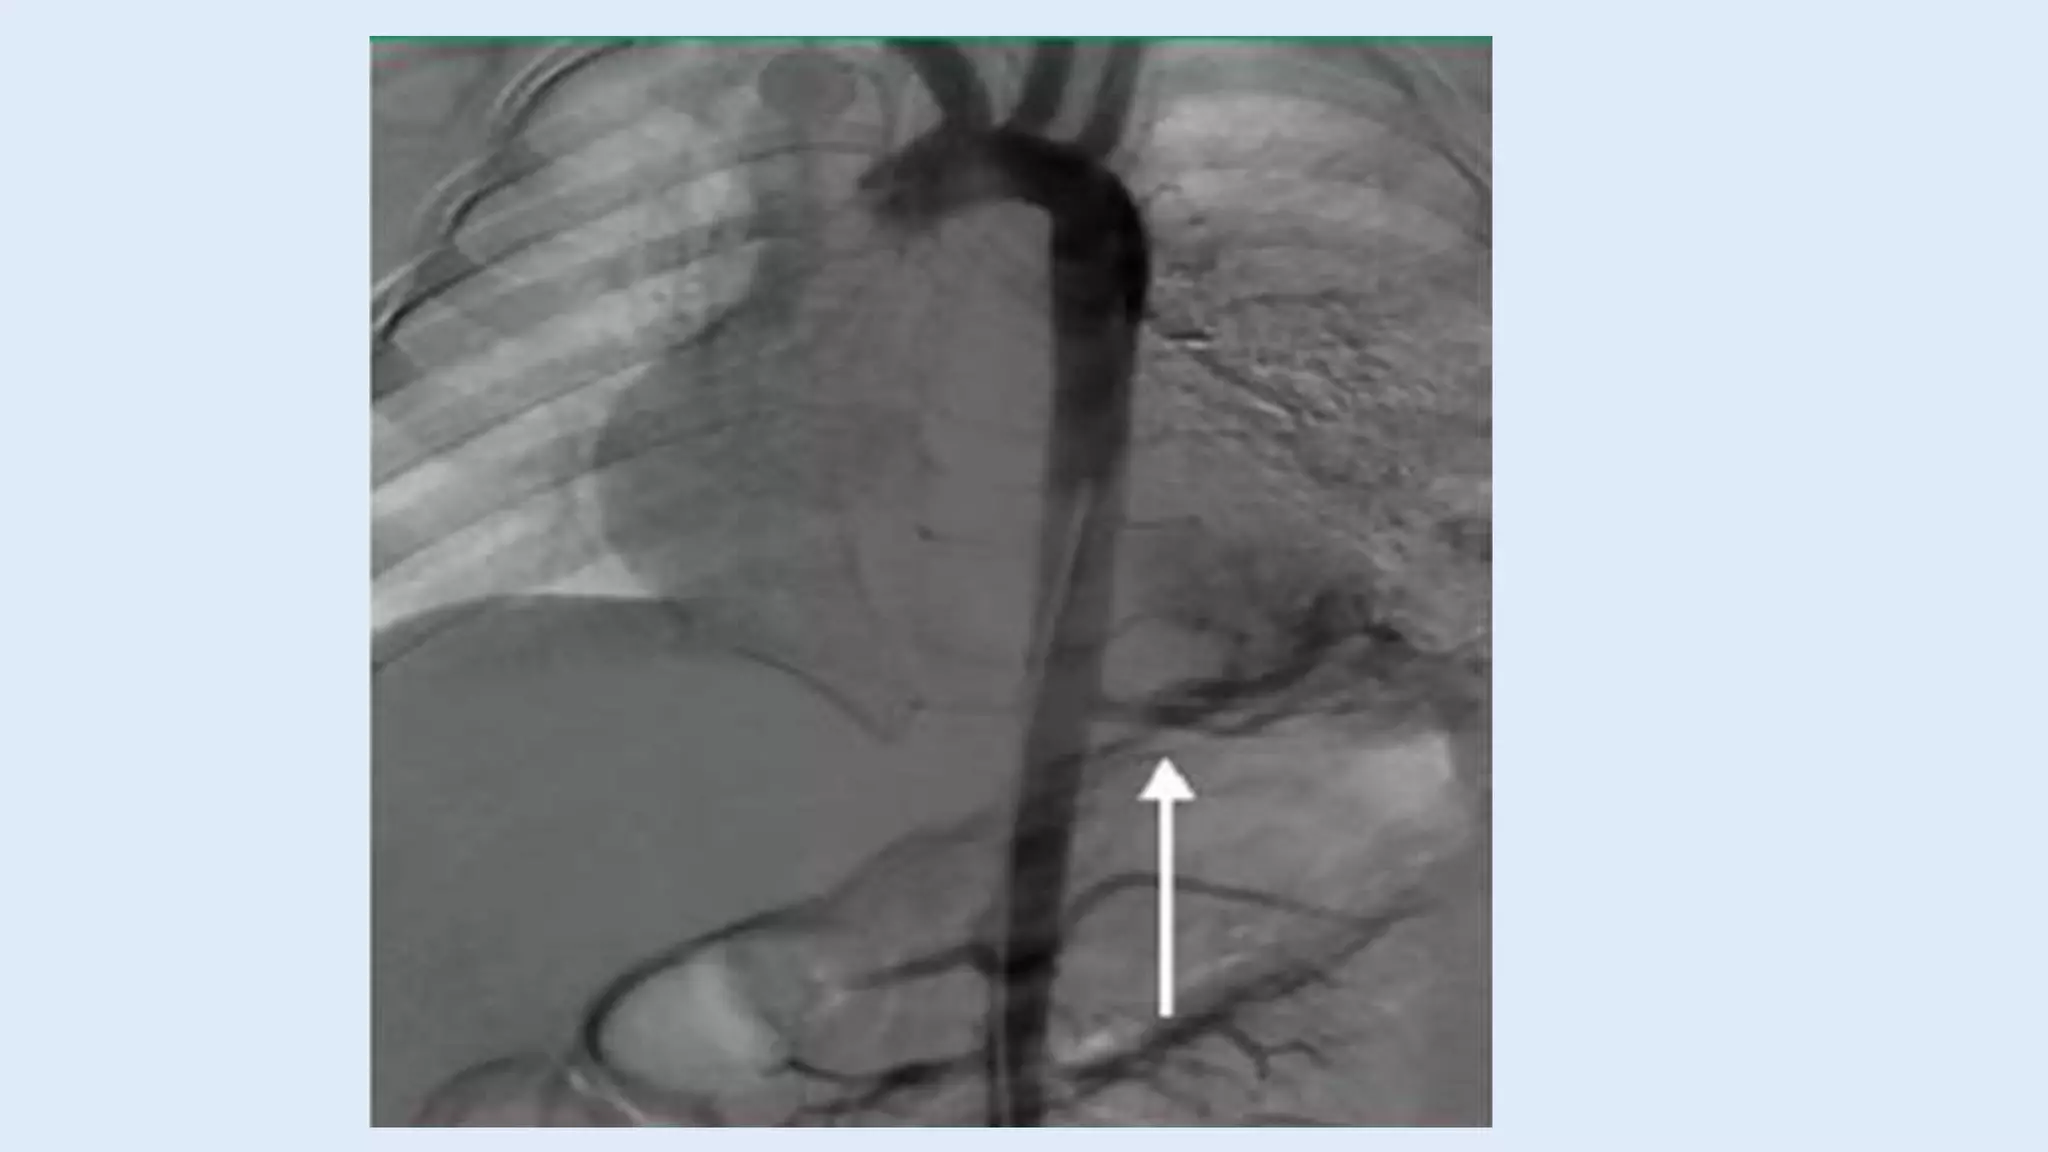

Angiography

• Traditionally, Angiography has been considered as the

gold standard for diagnosis of pulmonary

sequestration by virtue

• of its excellent depiction of the arterial and venous

anatomy

• Now it is replaced by multidetector CT or MRI

angiograph.

Angiography • Traditionally, Angiographyhas been considered as the gold standard for diagnosis of pulmonary sequestration by virtue • of its excellent depiction of the arterial and venous anatomy • Now it is replaced by multidetector CT or MRI angiograph.